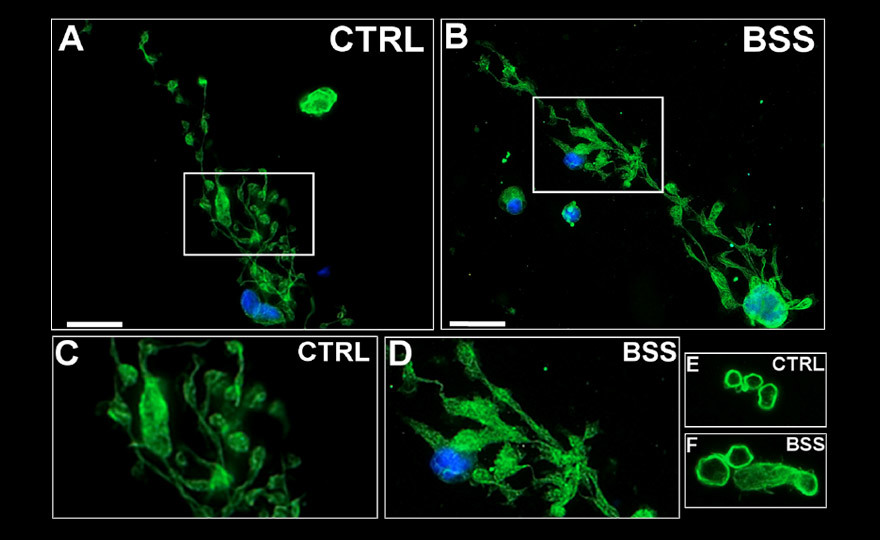

Aberrant proplatelet formation by megakaryocyte derived from patients.